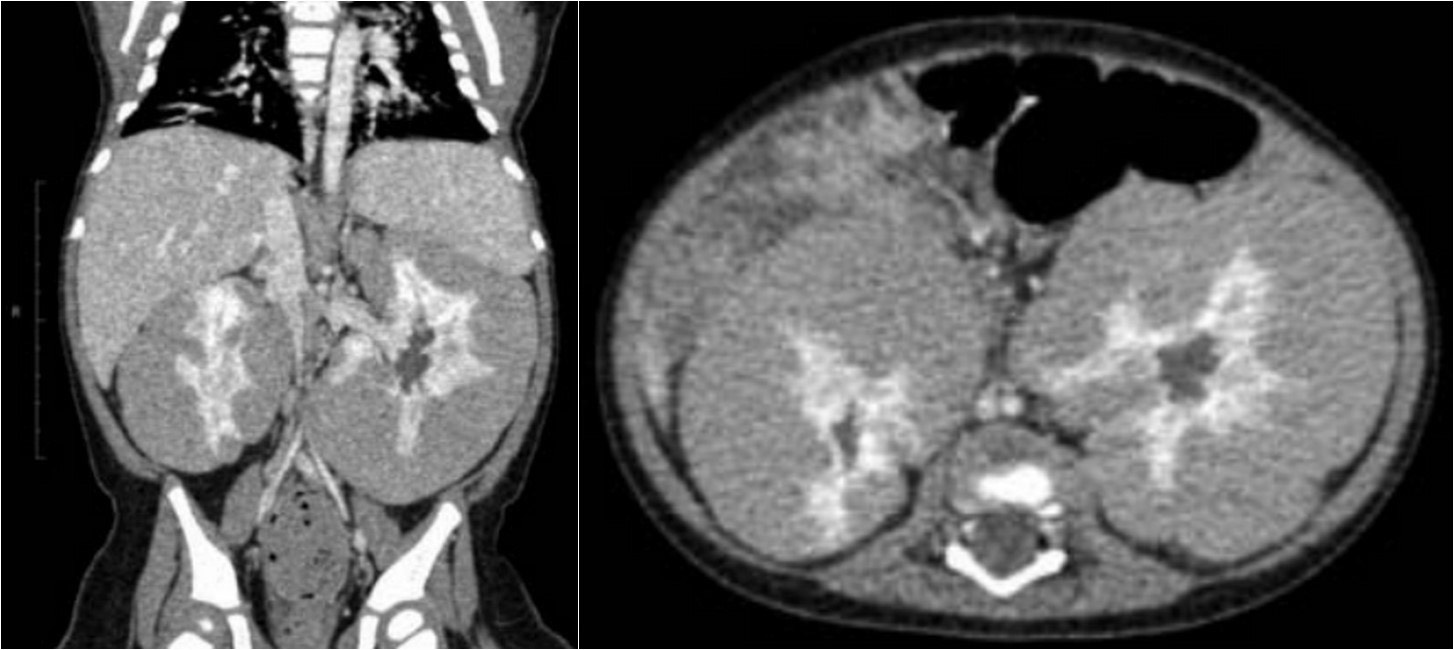

2967. Девочка 11 месяцев, жалоб нет, со случайной находкой в ходе планового осмотра, выполнена компьютерная томография с контрастным усилением, рентгенологическая картина соответствует